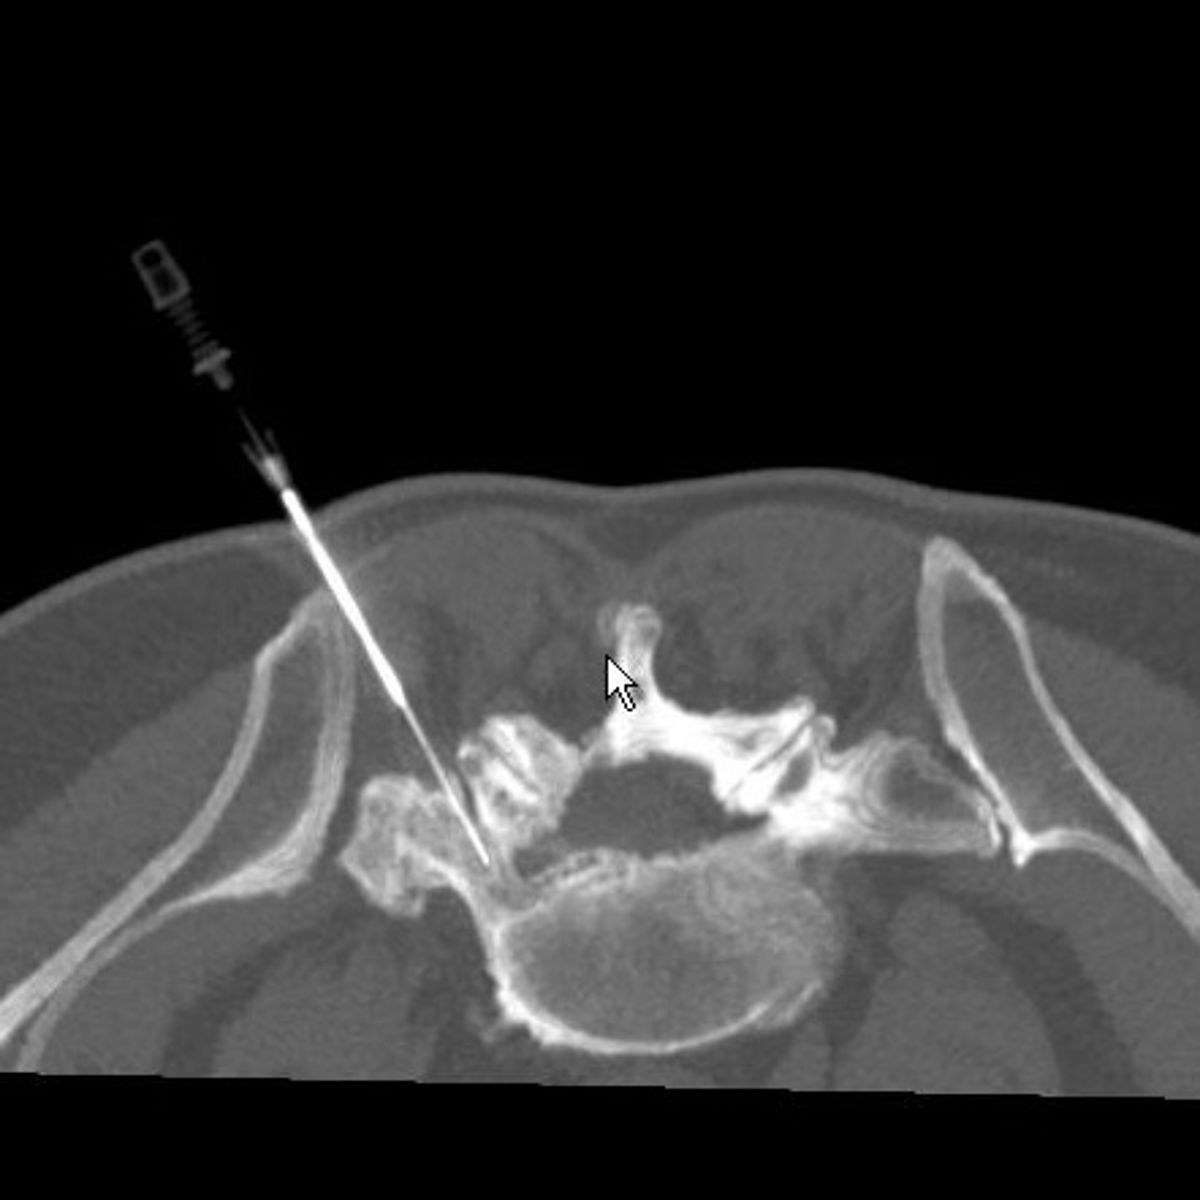

Zur Therapie stehen unsere modernen Großgeräte wie Computertomographen und Durchleuchtungsgeräte (Zwei-Ebenen-Angiographie) zur Verfügung, die schonendes und präzises Arbeiten im Millimeterbereich gewährleisten, was der Sicherheit und der Verbesserung der klinischen Ergebnisse für unsere PatientInnen dient.

- Minimalinvasive CT-gesteuerte Schmerztherapien

- Facettengelenksblockaden/-denervierungen